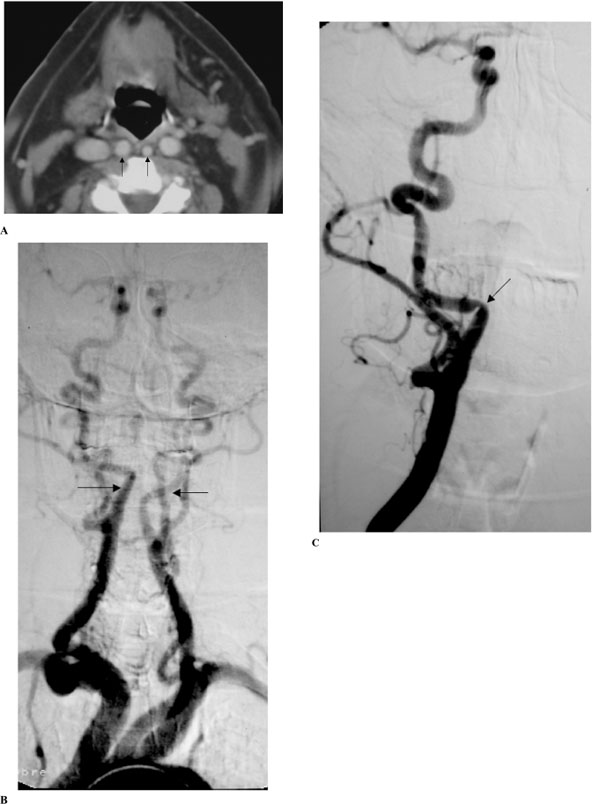

(A-C). Extended bilateral retropharyngeal course of both internal carotid arteries (kissing carotids), (patient #12).

A: Axial contrast CT scan in early-enhanced phase throughout the oropharynx. Notice medialization of both ICA’s reaching the retropharyngeal midline (arrows), and also medialization of both internal jugular veins.

B and C: Digital subtraction angiography in anteroposterior projection.

Upper aortogram of both ICA’s in the early arteriographic phase (B) shows bilateral medialization of the cervical segment of the ICA’s (arrows). Notice tortuosity of the proximal portions of the right common and external carotid arteries. Selective injection of the right common carotid artery in early arteriographic phase (C) shows progressive medialization of the proximal segment of ICA and then abrupt change in the course of the artery and then the artery regains its normal position after a short horizontal segment. Notice extrinsic arterial notch pinpointing the place of arterial course change and producing a focal non-atherosclerotic stenosis (arrow).

(Radiological classification of this patient was considered C,2.)